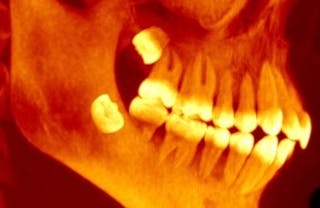

Wie die übrigen Zähne bilden sich auch die Weisheitszähne im Kieferknochen. Aber sie bilden sich erst sehr spät im Vergleich zu unseren anderen Zähnen.

Die Entwicklung der zweiten Backenzähne beginnt etwa im dritten Lebensjahr. Die Weisheitszähne beginnen oft erst im Alter von neun Jahren zu wachsen, aber es gibt große Unterschiede: Sie können schon im Alter von fünf Jahren ausbrechen und bis zu 15 Jahre alt sein. Sie brechen zwischen 17 und 24 Jahren aus dem Zahnfleisch aus, wenn nicht sogar noch früher.

Ein Zahn, der nicht richtig durch das Zahnfleisch und in den Mund durchbricht, ist „impaktiert“. Impaktierte Zähne können mit Problemen wie Zahnfleischerkrankungen, Zysten oder Schäden am zweiten Backenzahn in Verbindung gebracht werden.

Auch wenn Weisheitszähne anfangs schlecht angewinkelt sind, können sie sich drehen und ihre Position in den Zwanzigern oder Dreißigern verschieben.

Der Hauptgrund für eine Impaktion der Weisheitszähne ist Platzmangel im hinteren Teil des Kiefers. Unser Team fand heraus, dass, wenn sich die Weisheitszähne sehr spät entwickeln und durchbrechen, der meiste Platz bereits von den ersten und zweiten Backenzähnen beansprucht wird, so dass sich der Weisheitszahn nicht nach oben und durch das Zahnfleisch bewegen kann.

Ein verwandtes Problem ist das Kieferwachstum und die Gesamtlänge. Wenn der Kiefer nicht lang genug und schnell genug wächst, haben auch die sich später bildenden Weisheitszähne keinen Platz mehr und können nicht richtig oder gar nicht ausbrechen.